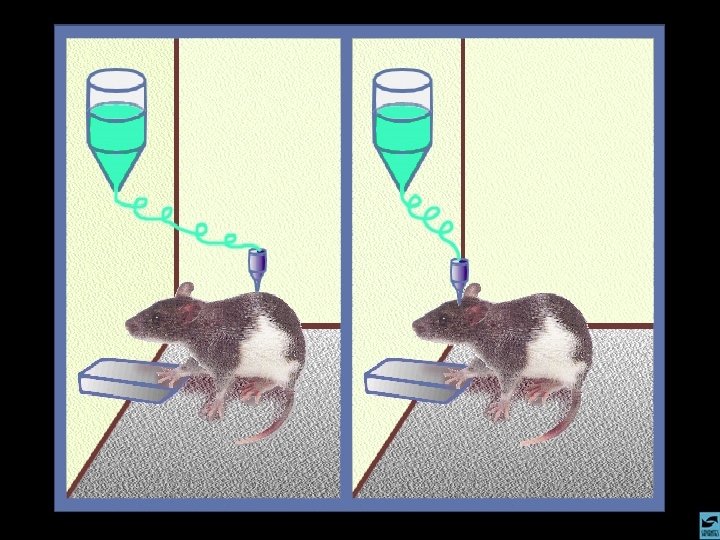

OS OPIÁCIOS INFORMAÇÕES GERAIS 1 - PODEM SER NATURAIS OU SINTÉTICOS 2 - SÃO UTILIZADOS NA MEDICINA COMO ANALGÉSICOS POTENTES 3 - CAUSAM INTENSA DEPENDÊNCIA FÍSICA 2 - MUITAS DEPENDÊNCIAS INSTALAM-SE NO USO CLÍNICO 5 - RAPIDAMENTE ESTABELECEM TOLER NCIA 4 - A HEROÍNA É UMA DROGA ILEGAL QUE ESTÁ RAPIDAMENTE DIFUNDINDO-SE